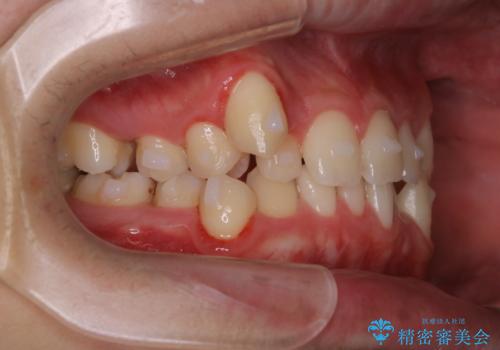

- マウスピース矯正中に、口臭が気になりクリーニングを行いたいとのことでした。染め出しをしての歯ブラシ指導とPMTC60分コースを行いました。

口腔内にはたくさんの細菌がいるため、ヌルヌルとしたプラーク(歯垢)が自然に歯の表面に付きます。

このプラーク(歯垢)にはたくさんの細菌が潜んでおり、虫歯や歯周病・口臭などの最大の原因です。そのため、毎日の歯磨きでプラーク(歯垢)をキレイに取り除くことが、健康な歯を保つためには欠かせません。